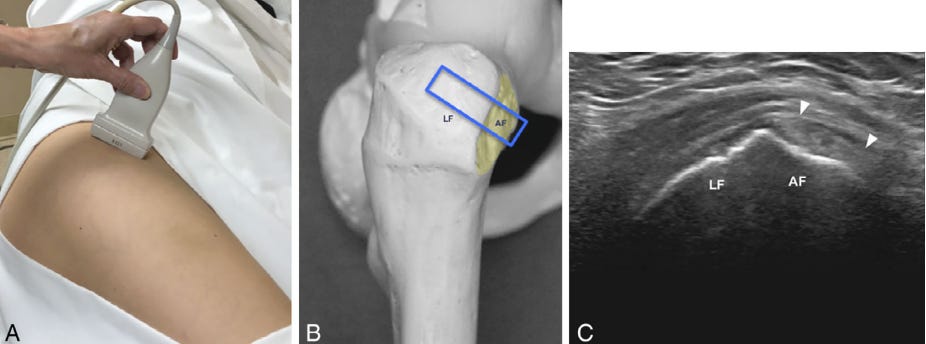

Posición del transductor e imagen en eje corto (SAX) del tendón del glúteo menor (GMIN).

A. El paciente se coloca en decúbito lateral, con la cadera ligeramente flexionada, una posición que los pacientes suelen adoptar de forma cómoda. El transductor se sitúa en un plano transversal oblicuo anatómico, orientándolo de forma perpendicular a la faceta anterior tanto en el plano transversal oblicuo como en el plano coronal oblicuo, tal como se muestra en el modelo anatómico de cadera en B (el rectángulo azul indica la posición del transductor). Nótese que el extremo posterior del transductor se rota en sentido cefálico, como se ilustra en A y B.

C. Imagen ecográfica correspondiente en eje corto (SAX) del tendón del GMIN, donde se identifica el tendón del glúteo menor hiperecogénico (puntas de flecha) situado por encima de la faceta anterior (AF).

LF: faceta lateral.